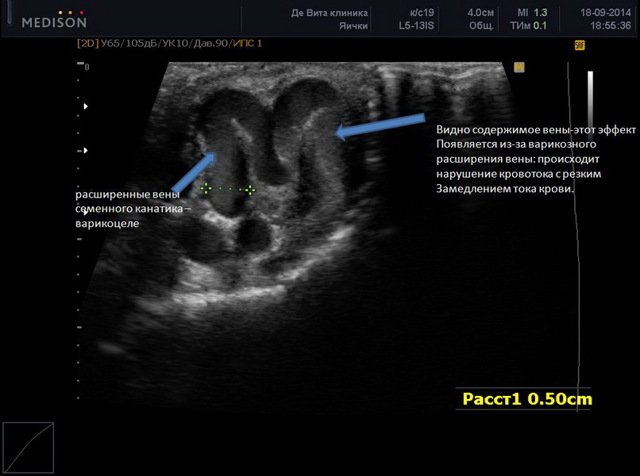

На стандартном УЗИ при варикоцеле определяются патологические изменения семенников, неоднородность паренхимы, увеличение или уменьшение половых желёз в размере. Однако сосуды визуализируются не столь отчётливо. Поэтому доктор может не диагностировать патологию в начальной стадии.

При ультразвуковом исследовании варикоцеле диагностируется, но не на ранних стадиях

Для точной диагностики проводится УЗИ с допплерографией сосудов мошонки. Этот метод позволяет распознать болезнь на ранних сроках, поскольку изображение на мониторе формируется благодаря волнам, отражающимся от кровеносного русла. Следовательно, визуализируются поражённые вены, неполноценные венозные клапаны и замедленный кровоток.